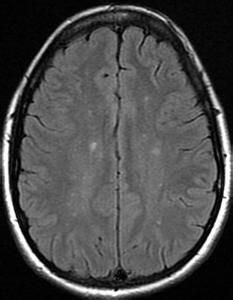

視網膜動脈變細中央動脈壓下降不能測出。輕壓眼球視網膜動脈即無血流,位置改變或視網膜中央動脈壓降低至眼壓水平時可見視網膜中央動脈搏動,血流呈節段狀。視網膜靜脈迂曲擴張,膨大呈豆狀或梭形,靜脈內血流呈念珠狀或節段狀血流緩慢自視網膜周邊部流向視盤毛細血管迂曲擴張,特別是在視盤表面及其周圍。視網膜周邊部早期有微血管瘤形成,也有位於後極部者。視網膜中央動脈和靜脈的吻合為本病最常見的體徵,約占81%,吻合可發生在眼底任何部位,但常見於視盤及其周圍,呈環形及花圈狀。隨病情發展吻合增加。視盤表面也可有新生血管形成,可呈桑椹狀或卷絲狀。新生血管也可發生在其他部位,如中周部。視網膜可有斑點狀或火焰狀出血,以及視網膜滲出。晚期可產生視神經萎縮,視網膜脈絡膜萎縮,色素沉著,動脈變細有白鞘,新生血管形成導致玻璃體積血,增殖性視網膜病變和牽拉視網膜脫離。

3.眼底螢光血管造影 臂-視網膜循環時間延長。視網膜動脈細,靜脈擴張,晚期血管壁有螢光素滲漏,毛細血管擴張充盈有微血管瘤形成呈現點狀強螢光。視盤表面新生血管呈花圈狀強螢光並有滲漏。可見動靜脈吻合支呈環狀吻合視網膜新生血管呈現強螢光,明顯滲漏。視網膜周邊部可見大片無灌注區其附近可見動靜脈短路。